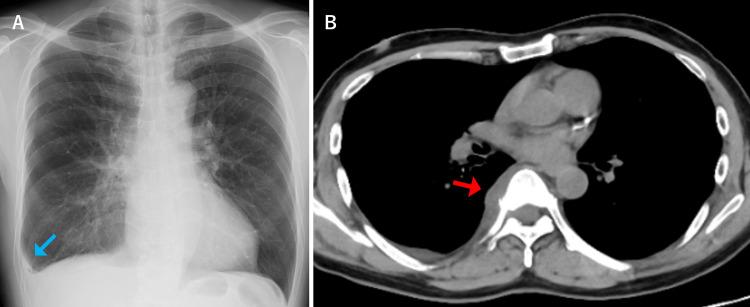

Pyogenic spondylitis typically presents with back and neck pain, fever, and fatigue. Sharp chest pain upon deep breathing, commonly associated with pleurisy, is not a typical manifestation of pyogenic spondylitis. We report a case of pleuritic chest pain as the initial presentation of pyogenic spondylitis. A 62-year-old male patient presented with a one-week history of right-sided pleuritic chest pain and fever. Chest computed tomography (CT) revealed a right pleural effusion. The patient was initially treated for bacterial pleurisy without improvement and subsequently developed back pain. Blood cultures yielded methicillin-resistant ( ​​​​). Additional thoracic spine magnetic resonance imaging (MRI) demonstrated pyogenic spondylitis with abscess formation on the right side of the vertebral body. The final diagnosis was pyogenic spondylitis that had progressed and spread inflammation to the pleura. This case highlights that pyogenic spondylitis can cause secondary pleurisy due to extension of inflammation to adjacent structures, a possibility that should be recognized. When  bacteremia is detected during the course of pleurisy, clinicians should consider secondary pleurisy and perform imaging studies to evaluate for pyogenic spondylitis.

化脓性脊柱炎通常表现为背部和颈部疼痛、发热及乏力。深呼吸时出现的尖锐胸痛,通常与胸膜炎相关,并非化脓性脊柱炎的典型表现。我们报告一例以胸膜炎性胸痛为首发表现的化脓性脊柱炎病例。一名62岁男性患者,有一周右侧胸膜炎性胸痛及发热病史。胸部计算机断层扫描(CT)显示右侧胸腔积液。该患者最初按细菌性胸膜炎治疗但无改善,随后出现背痛。血培养检出耐甲氧西林(此处原文缺失内容)。额外的胸椎磁共振成像(MRI)显示化脓性脊柱炎,椎体右侧有脓肿形成。最终诊断为化脓性脊柱炎,炎症进展并蔓延至胸膜。该病例强调化脓性脊柱炎可因炎症蔓延至相邻结构而导致继发性胸膜炎,这一可能性应得到认识。当在胸膜炎病程中检测到菌血症时,临床医生应考虑继发性胸膜炎并进行影像学检查以评估是否存在化脓性脊柱炎。